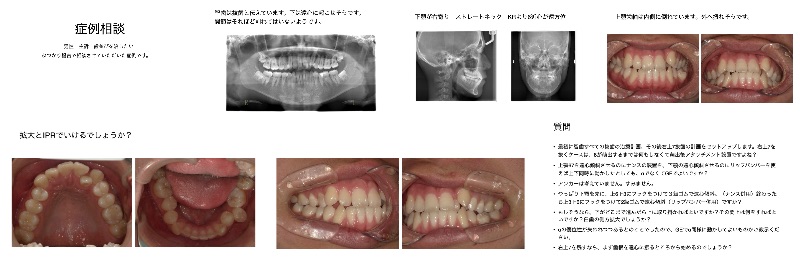

Q

K様スマーティーでです。

ストレートカット可能ですか?

なるべくアタッチメント減らしたいのですが

左下6欠損 インプラント予定です。

クリンチェックアドバイスお願いします。O様たびたび診ていただいてる患者様です。

アライナーずれてきました。 IPRのほうがいいですか?

クリンチェックアドバイスお願いします。O様下顎左右欠損なんですが これをつめるのは難しいですか?

アドバイスお願いします。すみません 可能なら10期に入れていただけますか

よろしくお願いいたします。 -